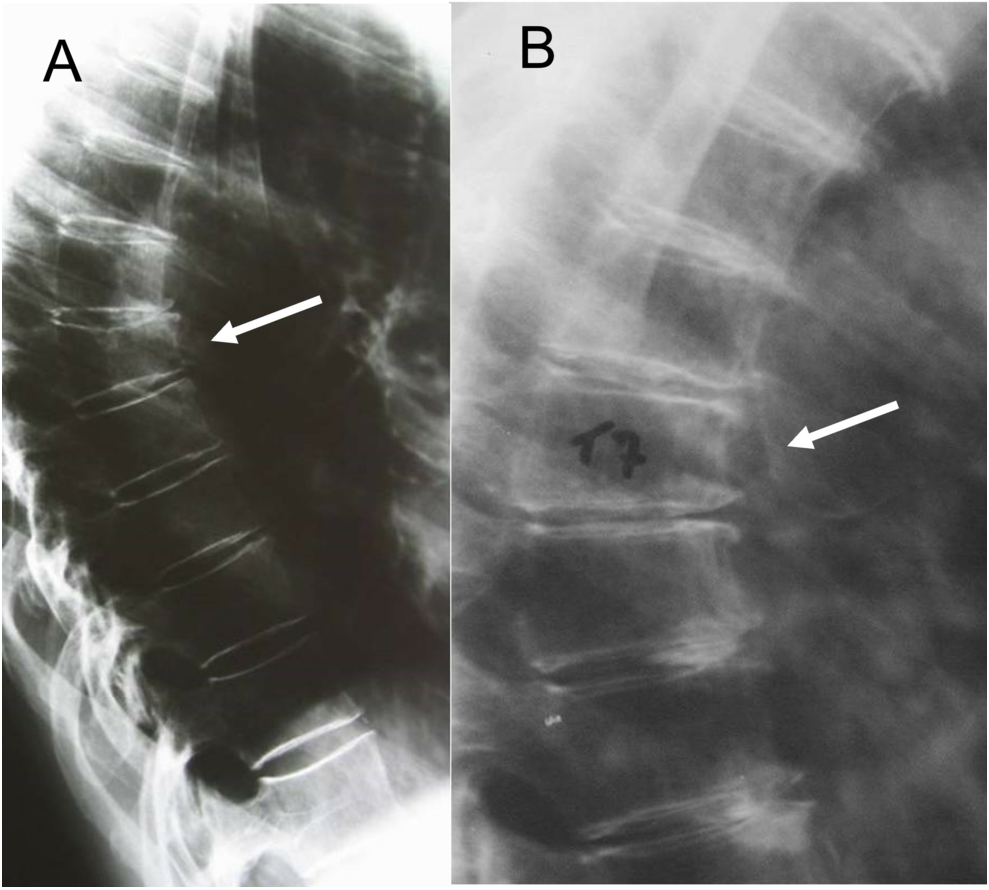

Results: On the shoulder, 10% of the tetraplegic athletes (sample of 10 rugby players) did present tendinopathies against 30% of those sedentary ones (sample of 10 tetraplegics). Joint strength, endurance and function were improved (sample of 17 subjects) by protocols of the rehabilitation programme of specific physiotherapy training of the scapula muscles making use of elastic bands. Rugby training also improved bone mineral content in the arms. On the elbow joint, clinical and radiological abnormalities (osteoarthritis, subclinical acute and chronic pain) were noticed in SCI patients, assessed through bilateral X-ray exams, on 10 paraplegics and 10 tetraplegics, such comorbidities being more evident (90%) on the latter pathology. Related to wrist and hand, SCI patients (8 paraplegics, 6 tetraplegics) presented minimal radiological signs of osteoarthritis.